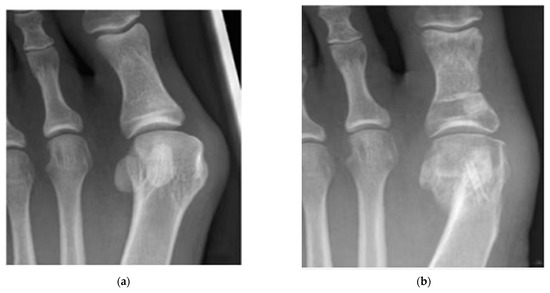

- Plaass, C.; von Falck, C.; Ettinger, S.; Sonnow, L.; Calderone, F.; Weizbauer, A.; Reifenrath, J.; Claassen, L.; Waizy, H.; Daniilidis, K.; et al. Bioabsorbable Magnesium versus Standard Titanium Compression Screws for Fixation of Distal Metatarsal Osteotomies—3 Year Results of a Randomized Clinical Trial. J. Orthop. Sci. 2018, 23, 321–327. [Google Scholar] [CrossRef]

| Mg-Y-RE-Zr screws | Bunion orthopaedics | 40 | Germany | 79% healing after 6 weeks, 90% healing after 12 weeks | [202] |

| Mg-Y-RE-Zr screws | Bunion orthopaedics | 100 | Germany | All healed | [202] |